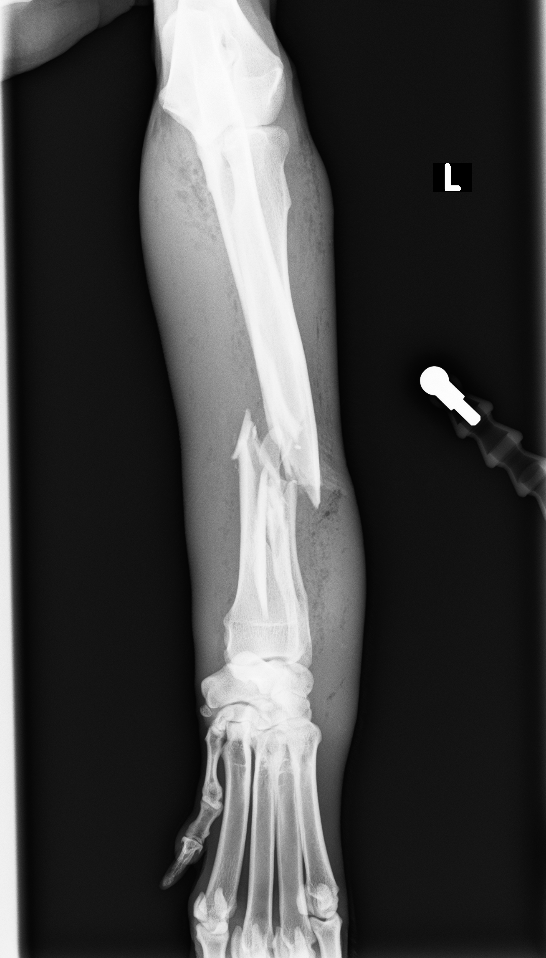

左前肢挙上し、軟部組織の腫脹が認められました。レントゲン、CT検査より橈骨・尺骨の粉砕骨折が認められました

診断と治療

左橈骨・尺骨の粉砕、解放骨折と診断し、橈骨にはLCPのダブルプレート、尺骨には髄内ピンによる治療を行いました

before